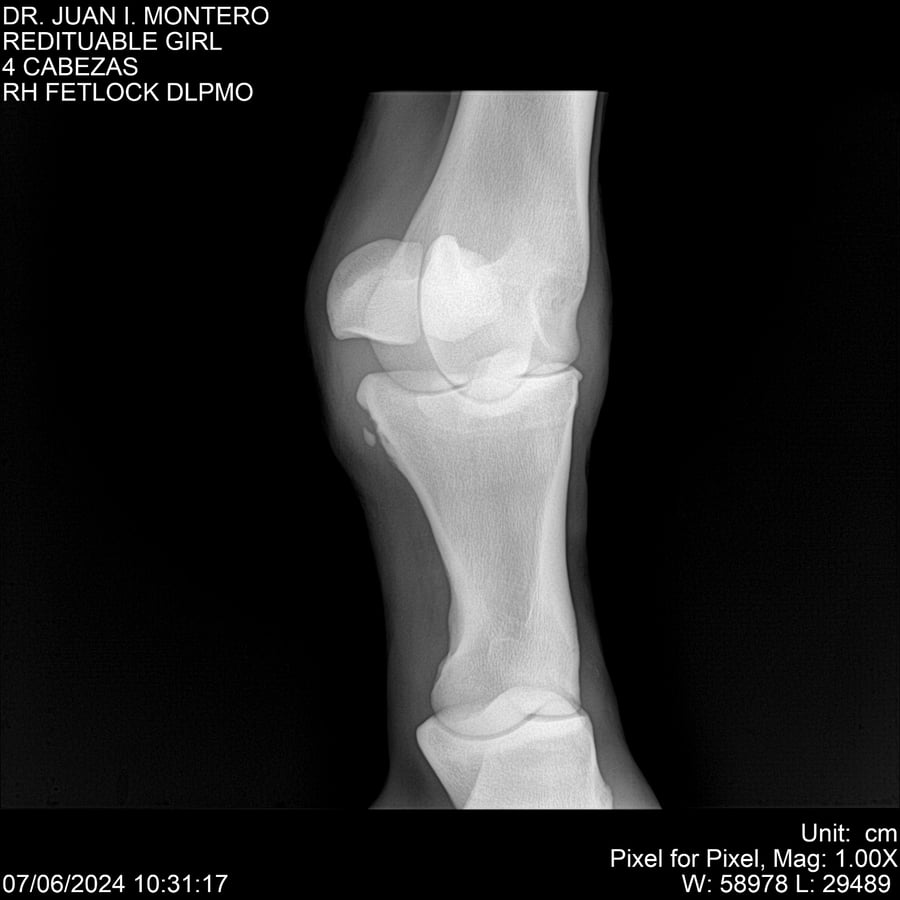

LOTE 19, REDITUABLE GIRL Lote Anterior Volver al remate Lote Siguiente Ficha Contacto Montevideo - Ficha del Lote Identificador: #281096 Categoría: Yeguarizos Montevideo - 79 Visualizaciones ClicData Contacto Empresa: Abelenda N. R., Walter Hugo Nombre*: Teléfono* : E-mail* : Mensaje Enviar Registrese gratis Este contenido Exclusivo está disponible sólo para usuarios registrados Ingresar